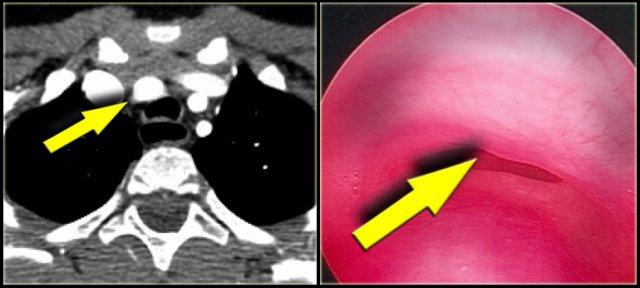

Right Arch with Aberrant left subclavian

The Right Aortic Arch with an aberrant left subclavian is an obstructing arch anomaly.

This also is a true ring.

The ligamentum ductus arteriosus between the arch at the level of the left subclavian artery and the left pumonary artery completes the ring.

If this ligament is very short, there will be a lot of compression.

On the left images of a symptomatic child.

On the axial image there is a right arch with the left subclavian artery that comes off on the posterior side and runs behind the trachea and the esophagus.

The compression of the trachea is demonstrated on the volume rendered view.